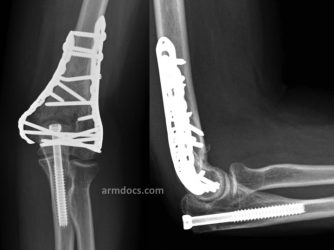

Appearance after fixation